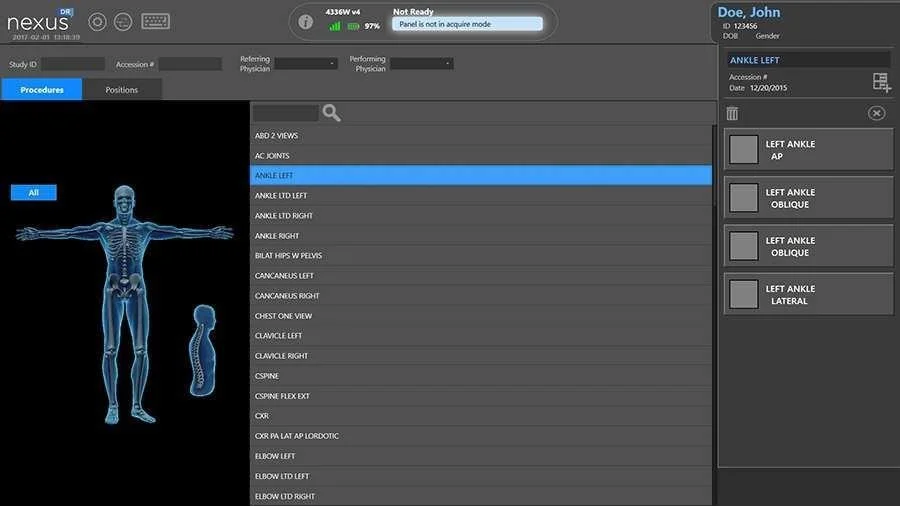

Интегрированная платформа для цифровой обработки изображений с централизованным управлением. Соответствие стандарту DICOM 3.0 для удобной обработки и хранения данных.

Эффективная обработка изображений позвоночника и нижних конечностей.

Интеграция с DICOM Worklist для автоматизированного выбора параметров. Возможность сохранения персонализированных настроек изображений.

Панорамная рентгенография позволяет получить полные снимки длинномерных объектов исследования (позвоночника и конечностей) путем сшивки (stitching) нескольких последовательных снимков исследуемого органа.

- Сшивка ,